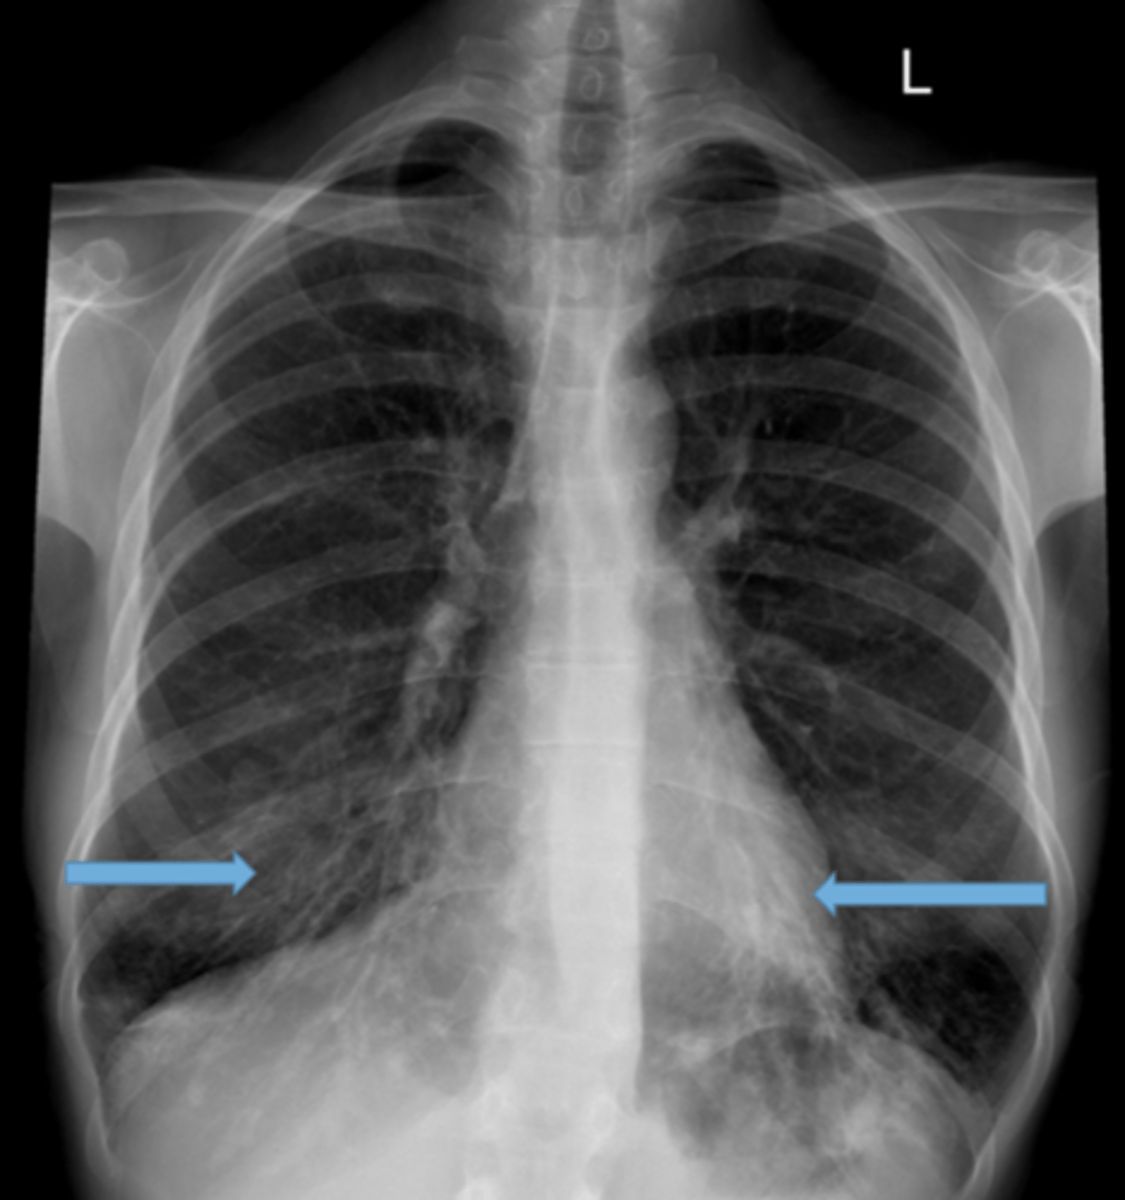

Pleural effusion

Pleural effusion

Pleural effusion (right sided)

congestive heart failure

congestive heart failure